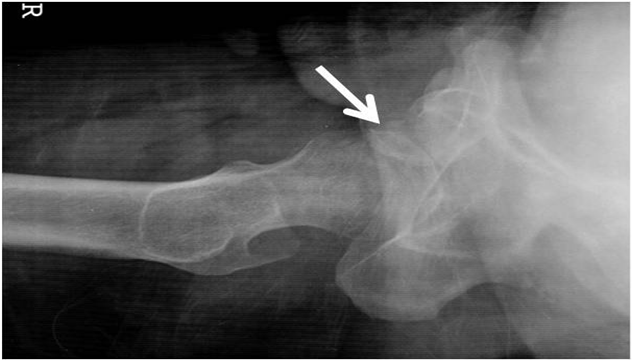

A 27-year-old man was injured by automobile accident and immediately presented to our emergency department. On physical examination, right hip was in flexion, external rotation and abduction. He complained of severe pain, and passive and active movements were not possible in right hip. There was neither neurovascular deficiency nor associated injuries. Radiograph of both hip revealed obturator dislocation of right femoral head and fractured femoral head fragment within hip joint (Figure 1). The dislocation was immediately reduced by traction in line of deformity followed by gentle adduction and internal rotation with pelvis stabilized by an assistant. After closed reduction, anteroposterior radiograph showed femoral head was reduced but crescentic radio-opacity was visible overlying femoral head and translateral radiograph revealed that the fractured femoral head fragment was turned inside out during closed reduction (Figure 2A & 2B). Computed tomogram depicted the 3-D configuration of fracture (Figure 2C & 2D).